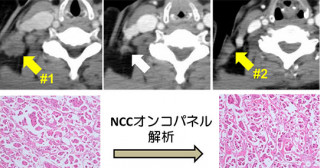

RET融合遺伝子上に生じるアロステリック効果を持つ二次変異 -分子標的治療薬に対するがんの新しい薬剤耐性メカニズムを発見-